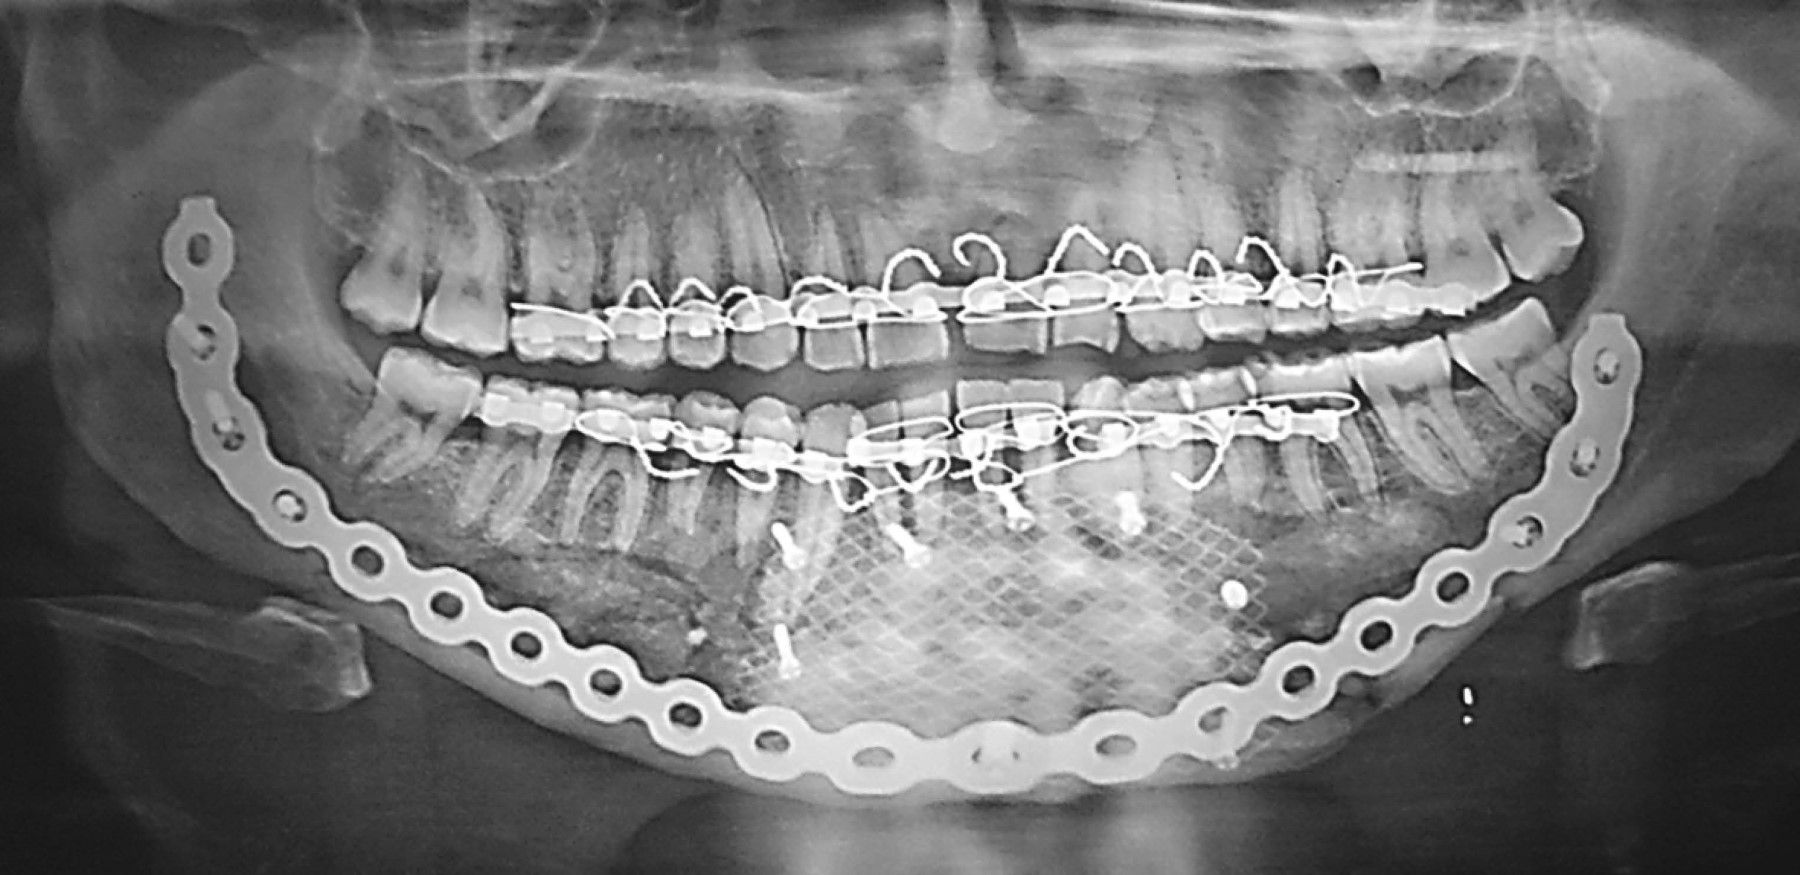

Dos días después del primer momento quirúrgico se seccionó la férula de resina y se realizó una fijación intermaxilar y tracción elástica hasta lograr el tripodismo dental en las siguientes 72 horas, aplicando los criterios biológicos de distracción osteogénica de Ilizárov, consistente en el trasporte gradual de los segmentos dentoalveolares para permitir la formación de tejido óseo en los espacios generados. Posteriormente se efectuó el segundo evento quirúrgico bajo anestesia general, con abordaje submandibular bilateral extendido desde la región antegonial de ambos lados, respetando las arterias faciales. Se realizó la disección de los tejidos hasta el plano óseo, localizando las estructuras óseas remanentes. Se colocó la placa de reconstrucción precontorneada con tres tornillos bicorticales a cada lado, procediendo luego a colocar un conglomerado biológico consistente en autoinjerto en bloques de cresta iliaca anterior izquierda y xenoinjerto particulado bovino más fibrina rica en plaquetas (FRP), revistiendo el lecho quirúrgico y cubriéndolo con una malla de titanio antes de la reposición y síntesis de los tejidos blandos (Figura 3).

El postoperatorio cursó sin complicaciones y se realizó un seguimiento de dos años sin presentar eventualidades, habiéndose restablecido la estética y función mandibular con una apertura bucal de 37 mm, una completa regeneración ósea y la preservación de todos sus órganos dentarios con oclusión estable (Figuras 4 y 5).

En el caso que describimos, además de la fijación rígida, también se utilizó una malla de titanio, siendo una buena alternativa para las FMC por la estabilidad tridimensional que provee y su adaptabilidad al contorno mandibular. Los orificios de la malla, asimismo, garantizan un suministro sanguíneo al hueso y los tejidos blandos subyacentes.15-17